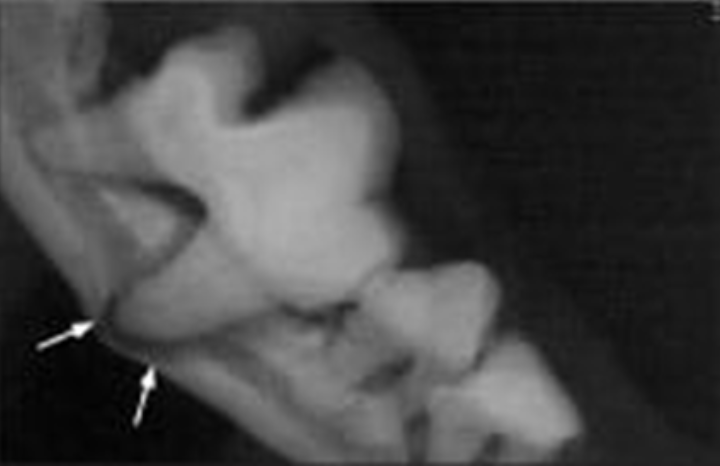

- 由於牙周囊袋寬度窄、牙結石阻擋或與鄰牙間空隙小,在探查過程中可能會遺漏。

- 貓咪和小型犬的下顎骨牙周疾病,可能會導致下顎骨脆弱,顯著提高拔牙過程中發生醫源性骨折的風險。術前使用牙科X光拍攝可以幫助醫生避免這種結果或是和飼主討論,提早告知可能發生的狀況。

- 當口腔的多個區域患有牙周疾病時,必須進行全口X光拍攝檢查才能一個個找出。

圖片來源:http://animaldentalservices.net/when-does-dr-startup-use-dental-x-ray/